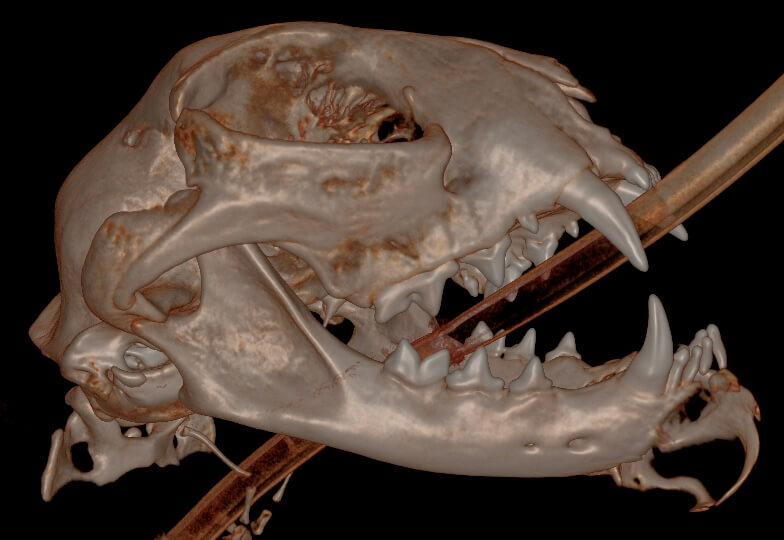

Bilateral rostral mandibulectomy was performed to excise the mass with submission to the oral pathologist (SOPA, www.sopforanimals.com). The mass was confirmed to be a FIOT (feline inductive odontogenic tumor) which does not spread to other organs but expands and is locally invasive requiring oral surgical excision. Margin mass excision was performed by removing the growth enblock extending to the middle of the left mandible and including the right canine (prevents impact with palate in the case of secondary mandibular drift).

Chin and lip tissues were preserved where possible as well as the sublingual salivary caruncles. The tongue side of the left mandible was partially preserved to allow for the remaining mandible segments to meet which will improve the long term occlusion/chewing capability. It is likely the patient will just be a normal cat with a short lower jaw length. The remaining lower cheek teeth were blunted to prevent trauma should one or both mandibles drift inward.

Histopathology confirms the diagnosis of feline inductive odontogenic tumor, which is histologically indistinguishable from an ameloblastic fibroma. FIOT/ameloblastic fibroma is a benign tumor of odontogenic epithelium that includes induced odontogenic mesenchyme. Because this lesion occurs almost exclusively in young animals, there is some possibility that is a hamartoma (i.e. proliferative developmental tumor) rather than a true neoplasm.

Complete excision is expected to be curative. In this case, the margin on the left is histologically “dirty” although this may not truly represent the biological margin. Overall, margins are promising since the neoplasm does not infiltrate soft tissues and the mass extends just to the margin where additional debridement of left mandibular bone may have removed small amounts of remaining neoplastic tissue. Close monitoring is advised.